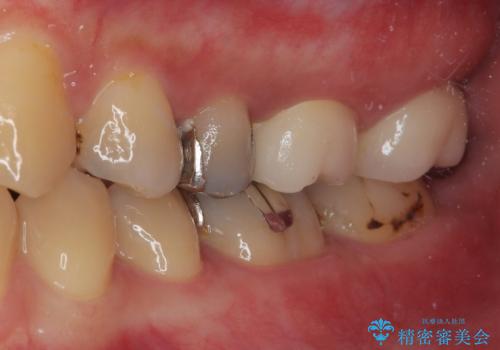

見た目、機能面共に満足していただけました。

今後もメンテナンスで通ってもらいながら、治療が必要になってきたところは順次行っていく予定です。

以前にも詰め物が外れてオールセラミッククラウンによる補綴治療を行っており、今回も詰め物の範囲が大きい為オールセラミッククラウンによる被せもの治療を行うことになりました。